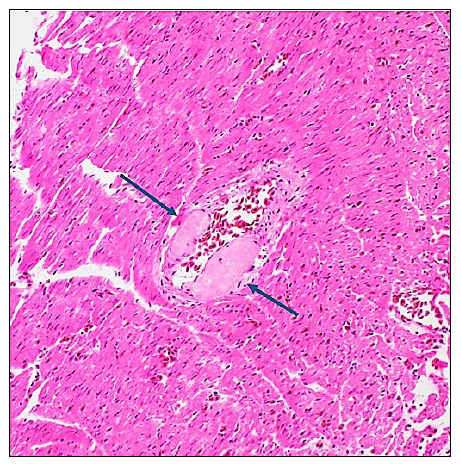

Figure 1: A myocardial vessel with multifocal distortion and thickening of the wall by brightly eosinophilic (pink) deposition of amyloid (arrows). H&E stain, 20x.

An 11-year-old Northern Saw-whet owl which had lived as a resident of a rescue organization was found deceased in its enclosure without premonitory signs. The animal had a history of arthritic change in several joints and bilateral cataracts, but was otherwise doing well. On gross examination, the coelom was noted to be mildly distended and contained clear, brown fluid. There was abundant fibrinous material over the surface of the liver. Histologically this correlated to a chronic perihepatitis. On histologic examination, it was also noted that the walls of numerous vessels, in particular the myocardium, had partial to circumferential thickening and distortion of the tunica media by the deposition of abundant acellular, brightly eosinophilic material (Fig. 1). Similar material was also found in the parenchyma of the spleen and the liver. This material-stained orange/red with Congo red special histologic stain, with bright green birefringence under polarized light (Fig. 2). This staining pattern is diagnostic for amyloid deposition, and confirmed amyloidosis in this owl.